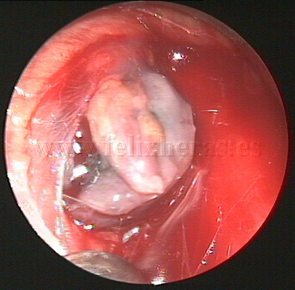

Adenopatías mediastínicas. Linfoma.

Videomediastinoscopia